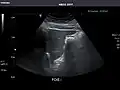

Kidneys: Right and left kidneys measure 11.5 cm and 12 cm in length respectively. No hydronephrosis. Small left lower pole kidney cyst.

Right kidney